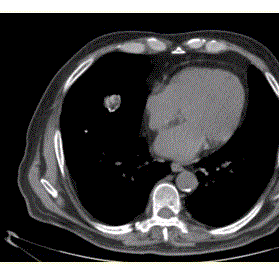

问题 患者男,体检时发现肺内结节,行CT检查如下图。应诊为

选项 A.结核球 B.周围型肺癌 C.炎性假瘤 D.错构瘤 E.钙化灶

答案 D